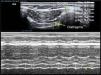

El grosor diafragmático es cuantificable de forma sencilla por ultrasonografía, siendo el hemidiafragma derecho, a través de su ventana hepática, más accesible que el izquierdo51. Para medir el grosor utilizaremos una sonda de 10-12MHz, colocándola de manera perpendicular sobre el 9.°-10.° espacio intercostal en la línea axilar anterior, para observar parte de la zona de aposición del diafragma con la caja torácica. En esta área, el diafragma se observa como 3 capas de distintas densidades dispuestas paralelamente (pleura, diafragma y peritoneo)51,70. El grosor diafragmático se mide mediante la realización de un modo M o con la imagen 2D durante una espiración no forzada (fig. 2). El grosor diafragmático normal en pacientes ventilados es de 2,4±0,8mm, indicando atrofia valores por debajo de 2 mm51. Se consideran valores normales ratios de 1,8, aceptándose como límite inferior ratios de 1,268.

Medición de la variación del grosor diafragmático mediante modo-M a nivel de hemidiafragma derecho. El diafragma se visualiza como 3 líneas paralelas: 2 hiperecogénicas con una central hipoecogénica y de mayor grosor. El número 1 representa el grosor inspiratorio y el número 2, el grosor espiratorio. La fracción de acortamiento diafragmático es la diferencia entre el grosor inspiratorio y el grosor espiratorio.

La variación del grosor diafragmático puede calcularse usando un modo M mediante la fórmula que se muestra en la figura 3. La variación del grosor diafragmático puede utilizarse como un indicador de la capacidad diafragmática para generar presión52,75. Una variación <20% podría ser considerada como un predictor de fracaso de la desconexión de la VM54, con una mejor predicción que el uso del índice de Tobin76.